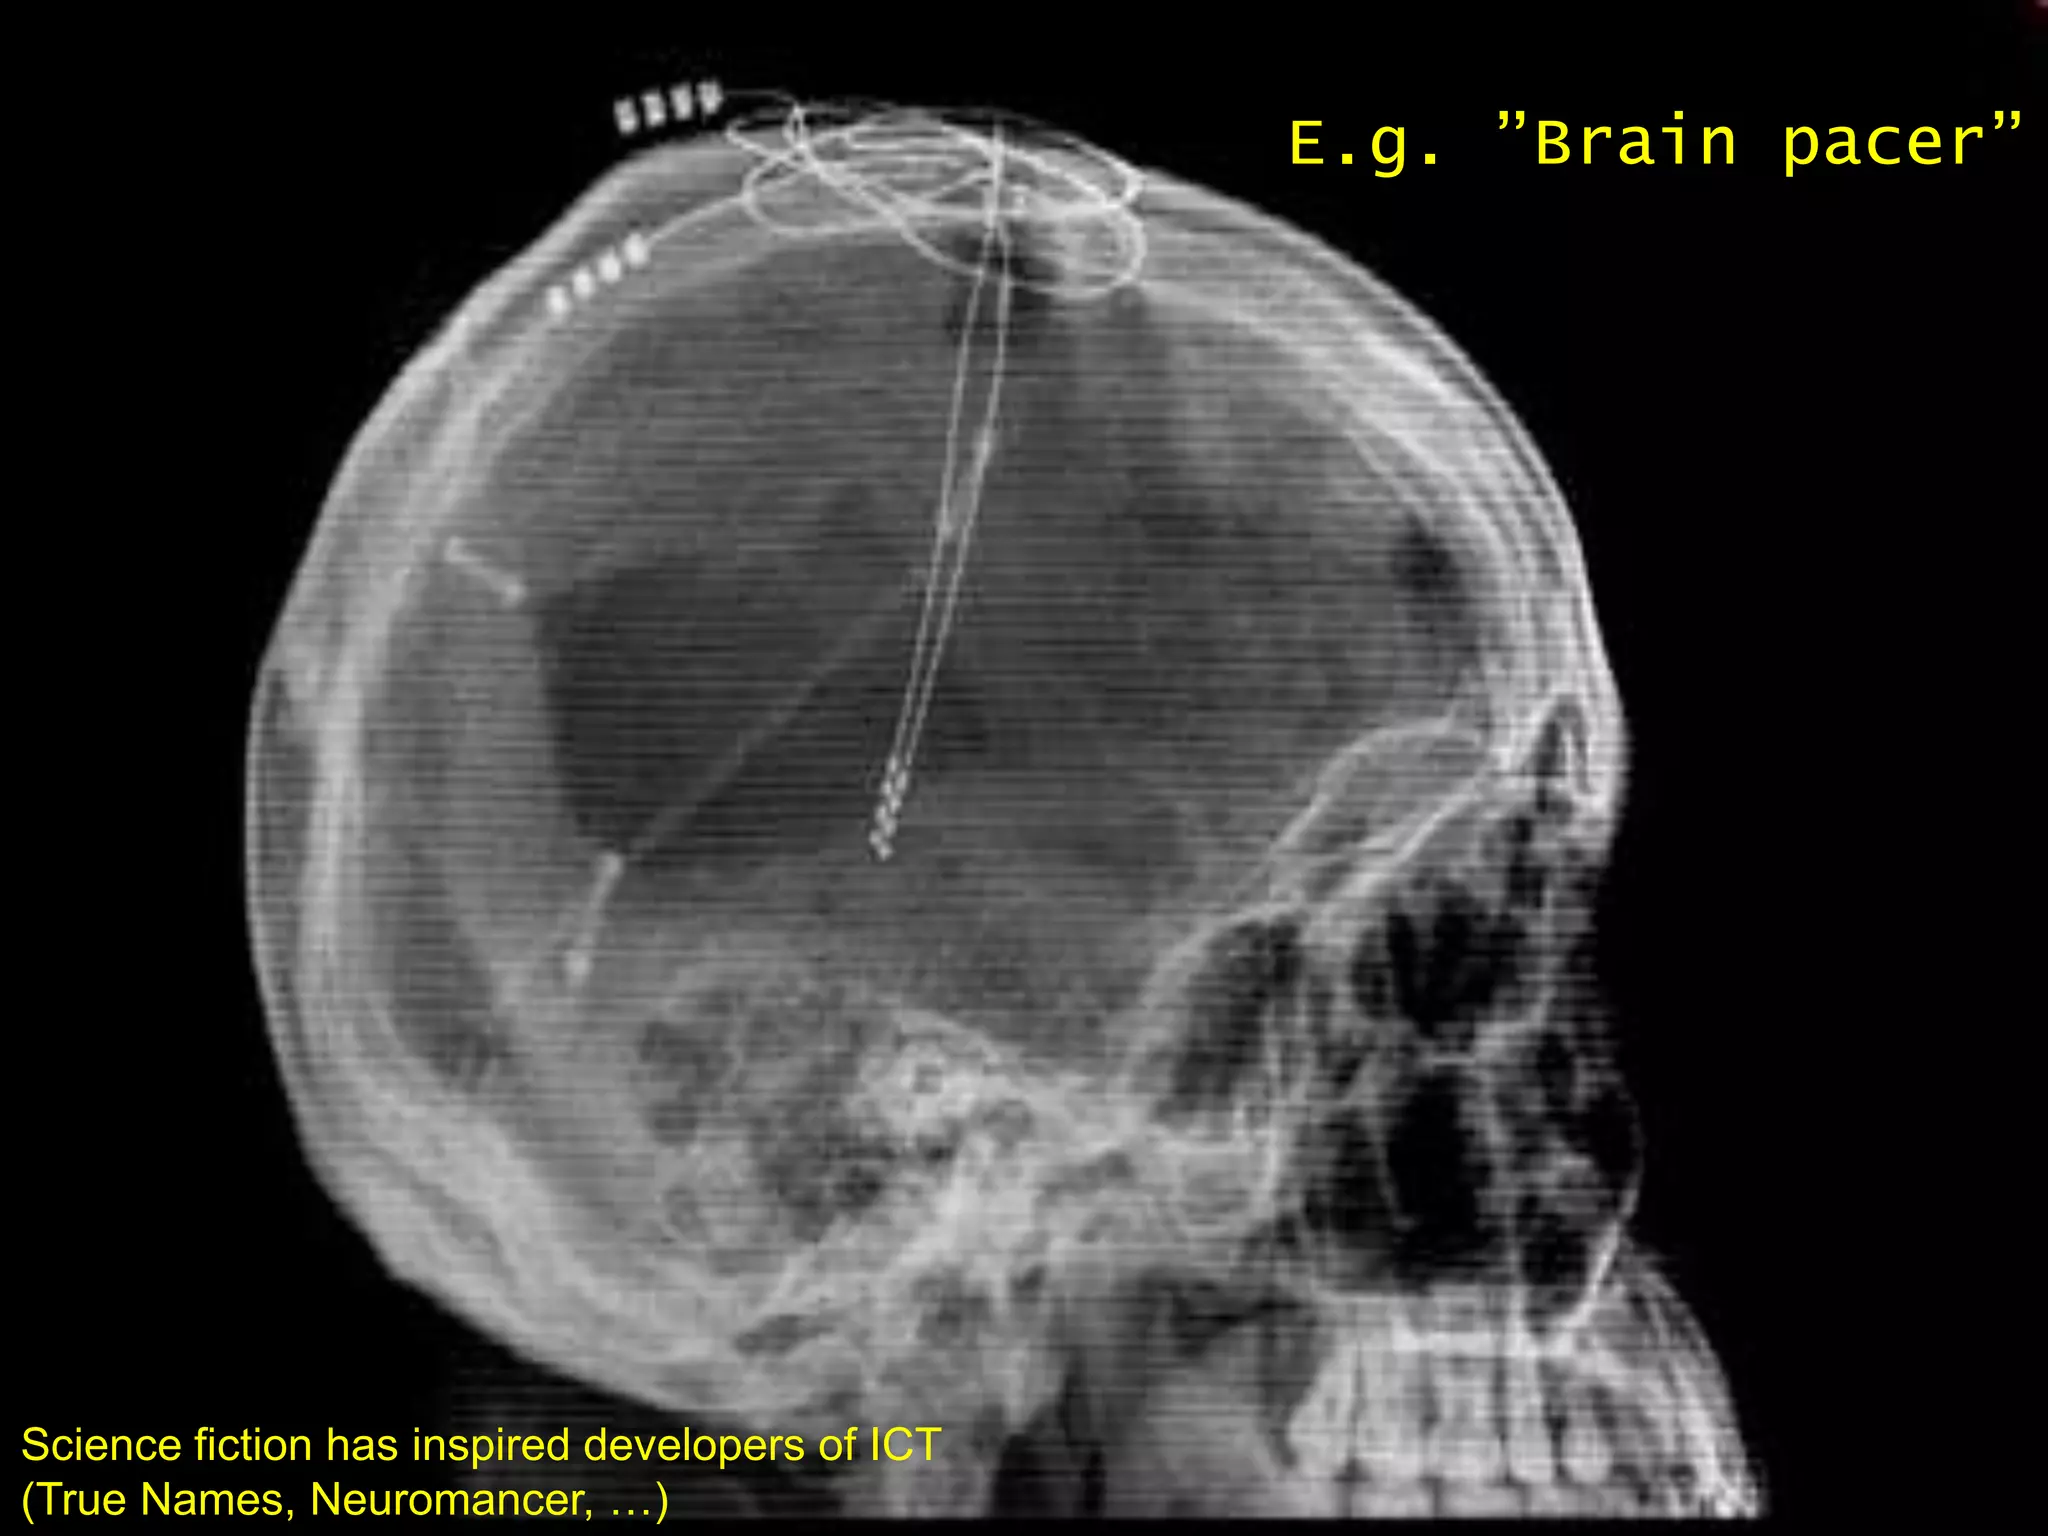

 Science fiction has often been more accurate than

respectable futures research

   True Names, Vernor Vinge.

E.g. ”Brain pacer”

Science fiction has inspired developers of ICT

(True24.9.2009 Neuromancer, …)